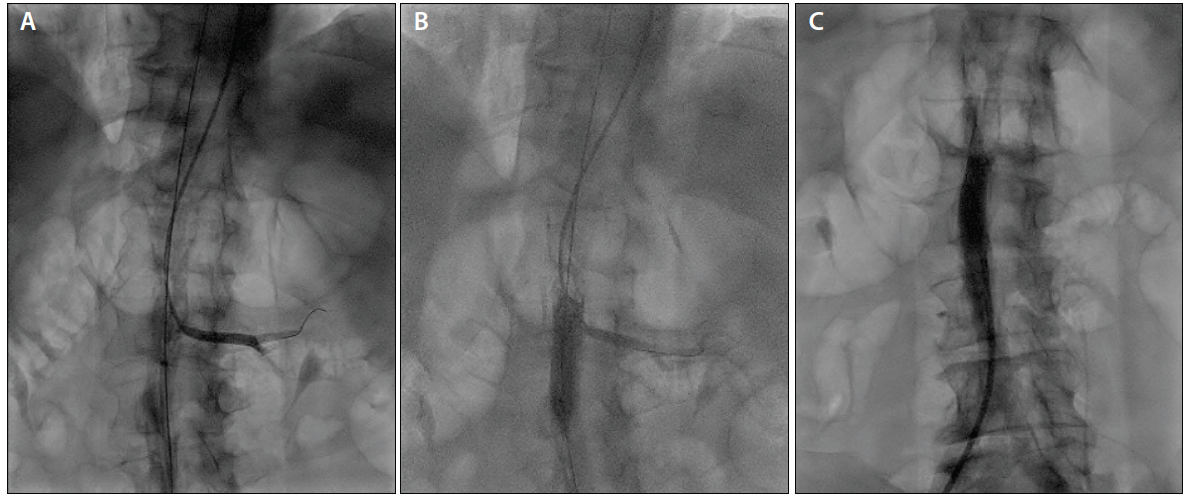

The patient began to complain of his usual back and leg pain shortly after sheath delivery. Although angiography demonstrated no injury to the aorta or its branches from placement of the sheath, it did confirm near occlusion of the infrarenal aortic lumen by the sheath. After careful consideration, the procedure was continued with a 7-F extra backup 3.5 guiding catheter to intubate the left coronary ostium. Dual-injection angiography of the LMCA and LIMA grafts was performed to define the features of the LMCA CTO (Figure 2). A recanalization attempt was undertaken; however, shortly after delivery of a retrograde microcatheter into the proximal LAD artery via the LIMA graft, the patient became profoundly hypotensive with marked ST-segment depressions. Despite supportive measures, the procedure was terminated due to the patient’s hemodynamic instability (secondary to microcatheter obstruction across a proximal LAD artery lesion). A reattempt of percutaneous coronary intervention (PCI) to the LMCA occlusion was planned using hemodynamic support with an Impella CP device (Abiomed, Inc.).

After PCI, the aortic lesion was definitively treated. From the radial approach, the LIMA guide was manipulated into the descending aorta and used to intubate the left renal artery. A balanced middle-weight wire was then advanced into the renal artery to mark it and provide an access rail in case of renal artery obstruction (Figure 4A). Next, from the femoral approach, peripheral intravascular ultrasound with angiographic coregistration was performed to define the precise proximal landing zone for an aortic stent. Finally, using the renal artery wire and angiographic coregistration images as markers, an 11-mm Viabahn VBX aortic stent was placed across the lesion (Figure 4B) and postdilated using a 12-mm balloon at low pressure to yield an excellent final result (Figure 4C).

Figure 4. Marking of renal arteries from the radial access with a workhorse wire and concurrent angiography from the femoral artery to illustrate aortic anatomy (A). Aortic stent deployment from the femoral approach with concomitant renal artery angiography from the radial approach, demonstrating renal artery patency after stent deployment (B). The final result in the infrarenal aorta (C).